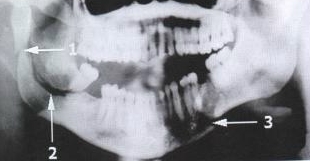

Standard Mandibular Series: Panoramic View

Single Most Useful Film In Diagnosis Of Mandibular Fracture

Fracture of Condylar Process, Ramus, Body Of Mandible